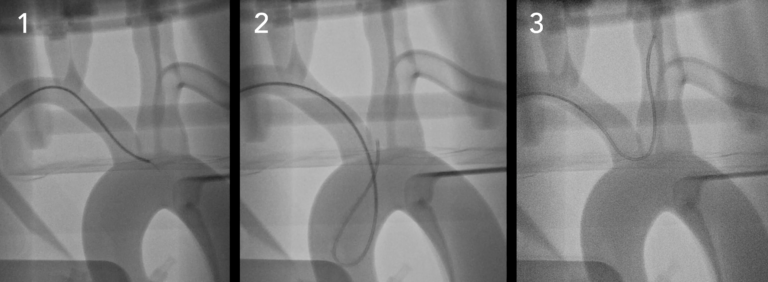

●具有清晰視野的多種成像模式– CT,熒光檢查和照相機(jī)

●執(zhí)行EVAR,TEVAR,F(xiàn)EVAR,TAVR等

SiM血管造影下的神經(jīng)徑向